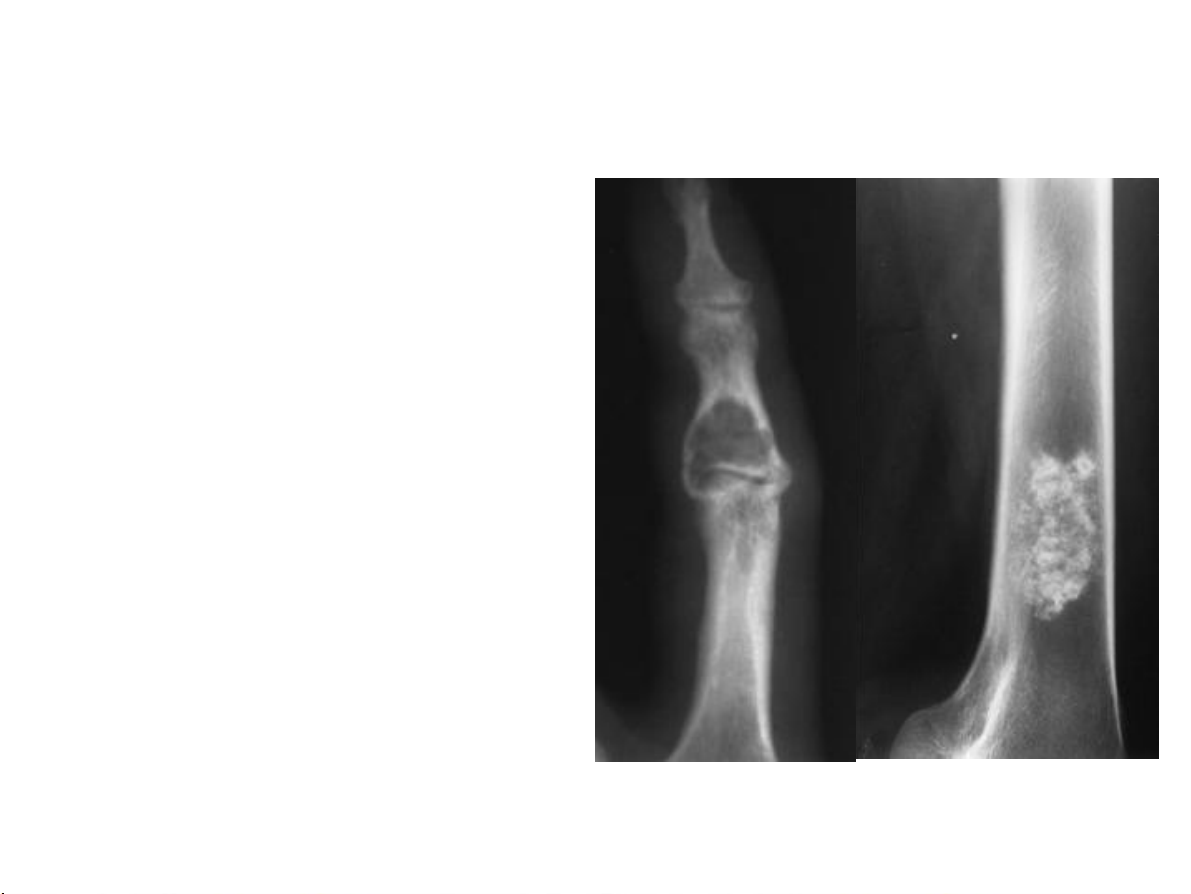

Bất thường về cấu trúc Huỷ xương 1.Giới hạn tổn thương 2.Phá huỷ vỏ xương: tổn thương ác tính? 31-Jan-23 CĐHA Cơ-Xương-Khớp

Vỏ xương: liên tục? Bị phá huỷ? Huỷ xương 1.Giới hạn tổn thương

1.Phá huỷ vỏ xương ác tính? 31-Jan-23 CĐHA Cơ-Xương-Khớp 31-Jan-23 CĐHA Cơ-Xương-Khớp 31-Jan-23 CĐHA Cơ-Xương-Khớp